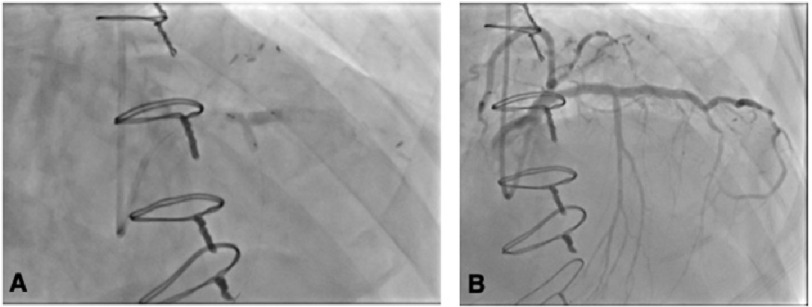

The LAD was stented with a 3.0 x 38 mm Resolute Onyx (drug-eluting) stent and was post-dilated with a 3.5 mm non-compliant balloon, yielding an excellent result and 0% residual stenosis. High-grade ostial stenosis of the first SPB branch was wired using a SuperCross® (90° ) microcatheter, and the ostium was ballooned through the stent struts. High-grade stenosis remained, so the first SPB was stented with a 2.5 x 8 mm Resolute Onyx® drug-eluting stent (DES), and kissing balloon dilation was performed in the LAD and first SPB. Excellent angiographic results were observed in the LAD and the first SPB, with 0% residual stenosis in the LAD and minimal residual stenosis at the ostium of the first SPB (Figure 3A, Figure 3B).

Figure 3. Coronary angiograms (right anterior oblique views) images.

(A) Kissing balloon dilation was performed in the LAD and first SPB with 0% residual stenosis in the LAD and minimal residual stenosis at the ostium of the first SPB. (B) Successful stenting of the LAD and first SPB.